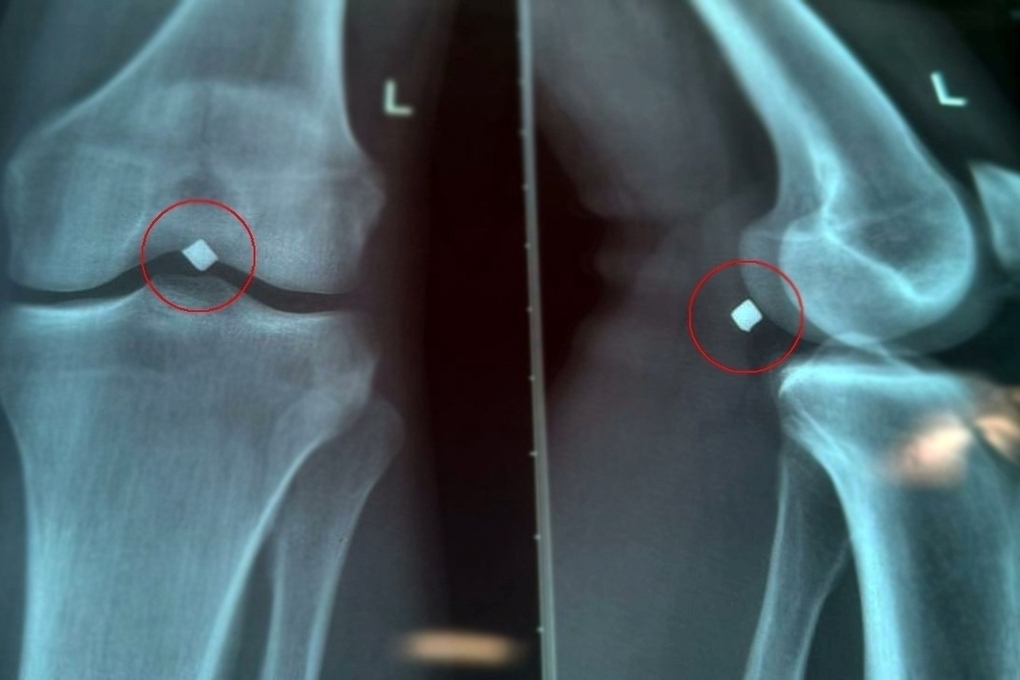

В больницу обратился 22-летний молодой человек, в июне этого года он получивший ранение осколком. Осколок пробил надколенник насквозь, прошел через полость коленного сустава и застрял в паре миллиметров от крупного сосудисто-нервного пучка.

«Провели обследование, рентген показал местонахождение осколка. Во время вмешательства выяснилось, что осколок лежал прямо на стенке подколенной вены и практически пролабировал ее, создавая прямую угрозу жизнеугрожающего кровотечения», — рассказал сердечно-сосудистый хирург Вячеслав Карпов.